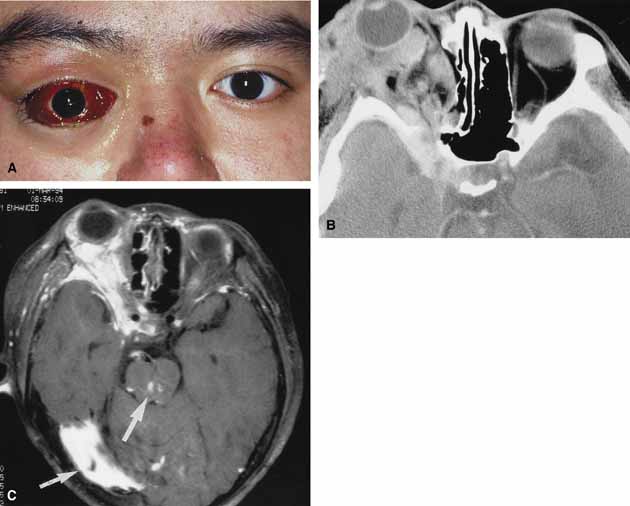

ORBITAL CELLULITIS Orbital cellulitis is the model for acute inflammation and a major cause of orbital inflammation in adults.2 It is characterized by a rapid development (over 1 to 2 days) of inflammatory signs and symptoms. These include: eyelid swelling, redness, warmth, pain, conjunctival injection, chemosis, proptosis, and mobility impairment with or without reduced vision. These patients generally feel unwell (malaise) and are febrile (Fig. 1A and 1B). The malaise and fever are key features in differentiating cellulitis from a rapid-onset nonspecific orbital inflammation (pseudotumor) and should be obtained from the patient's history. The majority of orbital cellulitis is secondary to extension from an adjacent sinus infection (Fig. 1C). Organisms gain access to the orbit directly through the thin ethmoidal bone, through congenital or acquired dehiscences in the thin orbital walls, pass through preexisting orbital foramina, pass retrogradely through the valveless venous orbital system, or along the veins as a periphlebitis. Orbital cellulitis may also be secondary to an endophthalmitis, systemic bacteremia (e.g., after dental work), infection of a nearby skin wound, dacryocystitis, or penetrating trauma. The history and physical examination are crucial in distinguishing between preseptal and true orbital cellulitis. The orbital septum delineates the anterior eyelid soft tissue from the orbital soft tissue. Infections anterior to the septum are classified as preseptal cellulitis while those posterior to the septum are termed orbital cellulitis. Recognition of true orbital involvement is important not only because of the threatened visual loss associated with the orbital involvement but also because of the potential for central nervous system complications including cavernous sinus thrombosis, meningitis, and death. Preseptal cellulitis is characterized by lid edema, erythma, and discomfort. Inflammation posterior to the orbital septum (orbital cellulitis) is heralded by the development of pain, chemosis, proptosis, motility disturbance, and visual deterioration. The extent of ocular involvement in preseptal and orbital cellulitis can be determined by assessing visual acuity, extraocular motility, pupillary reaction, color vision, confrontation visual fields, intraocular pressure, and optic nerve head appearance. Evidence of facial/head trauma or surgical wounds may be apparent. Constitutional signs such as fever, lethargy, and irritability should be sought. The examiner should assess for meningeal signs and neurologic defects. After the initial examination, the physician should follow patients with orbital cellulitis with at least daily assessments of visual acuity, motility, and pupil reaction. Progression of the disease process despite appropriate antibiotic therapy suggests abscess formation. Orbital abscesses may be either localized, diffuse, or subperiosteal (Fig. 1C). Subperiosteal abscesses most commonly occur along the medial wall and may expand rapidly, compromising optic nerve function even in the absence of many signs of infection.3–6 Several mechanisms may contribute to visual deterioration including direct optic nerve compression, elevation of the intraorbital pressure, and proptosis causing a “stretch” optic neuropathy. Clinically, the eye typically is displaced away from the subperiosteal abscess, and orbital imaging shows a convex mass adjacent to the involved sinus. Orbital infection with potential orbital abscess formation occurs when bacteria break through the periorbita and gain access to the extraoconal or intraconal space. Diffuse or localized orbital abscess formation may also lead to visual loss through an increase in intraorbital pressure, posterior ischemic optic neuropathy, optic nerve inflammation, or vasculitis. Acute visual loss in the presence of an orbital infection is almost always a surgical emergency in which immediate drainage of the abscess is required to save vision. Continued posterior extension of the infection may result in an orbital apex syndrome, decreased function of cranial nerves,2–6 thrombosis of the cavernous sinus, and even death. Hallmarks of cavernous sinus thrombosis include cranial neuropathy and central neurologic impairment.7 Organisms responsible for orbital cellulitis vary widely and may include Staphylococcous aureus, Streptococcus species, as well as a mixture of aerobes and anaerobic organisms. Recent studies indicate that streptococcus is the most common cause of orbital cellulitis associated with sinusitis in children.8 With increasing age the pathogens increase in complexity. In patients older than 15 with subperiosteal abscesses, polymicrobial infections are typical with anaerobes cultured in every case.5 Orbital imaging in the axial and coronal plane should be obtained in all patients suspected of having orbital cellulitis. Computed tomography (CT) is preferred to magnetic resonance imaging (MRI) because the orbital tissues have higher contrast and bone is well visualized. Axial CT views allow evaluation of the medial orbit and ethmoid sinuses, whereas coronal scans image the orbital roof, floor, frontal, and maxillary sinus. A subperiosteal abscess appears as a homogeneous opacification between the orbital wall and the displaced periorbita.6 Contrast agents are not necessary to visualize a subperiosteal abscess. Management of orbital cellulitis is dictated by the rapidity of onset. Oral antibiotics may be appropriate for mild cases whereas intravenous antibiotics are required for more fulminant cases. Antibiotic coverage should be broad spectrum and include coverage for gram-positive organisms and anaerobes. Examples include cloxicillan and clindamycin or a late-generation cephalosporin and clindamycin. In those patients allergic to penicillin agents, erythromycin and clindamycin or vancomycin and clindamycin are considerations. Most patients with orbital cellulitis also benefit from a nasal decongestant as well as an oral decongestant and warm compresses to the affected site (10 minutes out of every hour). Daily or more frequent reexaminations are required depending on the fulminancy of the disease. Once antibiotics are initiated, a 24-hour wait-and-watch period is generally observed (unless the process is aggressive and rapidly developing). If there is no progression at 24 hours and the vision is stable, continued observation is appropriate. If the orbital cellulitis is rapidly developing and fulminant, frequent assessments (every 2 to 4 hours) are required. If the vision, motility, or neurologic status is deteriorating, immediate surgical intervention may be required. The indication for surgery in a patient with orbital cellulitis has been controversial over the years. The simple presence of a subperiosteal abscess (SPA) was at one time an indication to drain but this is no longer always the case. Providing the vision is normal, the SPA may resolve with medical management. The clinical course, and not the radiographic appearance should dictate management.5,6,9 Surgical therapy may be influenced by many factors including the visual status, size, and location of the SPA; intracranial complications; the sinus involved; the presumed pathogenesis, and the anticipated bacterial response to antibiotic treatment.10 Immediate drainage of SPAs and sinuses is recommended for patients of any age whose vision is compromised. Urgent drainage (as soon as practical) should be considered for large SPAs, extensive superior or inferior abscesses, intracranial complications at the time of presentation, frontal sinusitis where the risk of intracranial extension is increased, and in those suspected of having anaerobes (postdental procedures). However, cookbook approaches should never take the place of good clinical judgement and therapeutic decisions regarding early drainage versus medical management with observation are ultimately up to the managing physician.10 Older children (older than 9 years of age) and adults benefit from early surgical drainage. Although surgical treatment does not guarantee rapid resolution, a complicated course is more likely without it.10 Abscesses may also develop within the intraconal space. The prescence of an abscess within the orbital tissue coupled with any signs of visual loss, afferent pupillary defect, or a significant motility defect should prompt emergent surgery. If visual acuity is stable and extraocular motility essentially full, initial treatment may consist of empiric antibiotic therapy and close observation with serial CT scans. The prescence of neurologic symptoms such as altered mental status or seizures implies intracranial extension with potential intracranial abscess. Infection may spread from the sinuses to the intracranial cavity via retrograde thrombophlebitis, directly through osteitic bone or from congenital or acquired bony defects. In the past, intracranial abscess formation had a poor prognosis with a high mortality rate. Successful management of suppurative abscesses requires early recognition of the disease process, intravenous antibiotics, serial neuroimaging, and surgical management of at least the orbit and sinus disease and often the intracranial disease.11 PHYCOMYCOSIS (RHINO-ORBITAL MUCORMYCOSIS AND ORBITAL ASPERGILLOSIS) Rhino-orbital mucormycosis, a fungal infection of class Phycomycetes and order mucorales, is notable for its high morbidity and mortality.12,13 Orbital involvement is an acute, aggressive, and often lethal infection if not recognized early. Phycomycetes (common bread molds) are ubiquitous fungi occurring in soil, air, skin, body orifices, manure, and food including fruit.13 Inoculation occurs by inhalation reaching the nasopharynx and oropharynx. At this stage most patients are able to contain the disease. However, individuals whose cellular and humoral defense mechanisms have been compromised by disease or immunosuppressive treatment may not be able to generate an adequate response. The fungus may then spread to the paranasal sinus, orbit, meninges, and brain by direct extension.13 Mucormycosis preferentially involves blood vessel walls resulting in vascular occlusion, thrombosis, and infarction.14 This frequently affects the ophthalmic artery and in more serious cases may involve the internal carotid artery and cavernous sinus. Although there have been a few reports of mucormycosis occurring in healthy individuals, virtually all other patients have had previous severe underlying disease. The patient most vulnerable to this infection is an one with uncontrolled diabetes with ketoacidosis. A host of other conditions also predispose patients to the disease including: multiple myeloma, lymphoma, organ transplantation with immunosuppresion, chemotherapy, corticosteroid treatment, acquired immunodeficiency syndrome, etc.(Fig. 2A).12–14 Mortality is extremely high for patients with phycomycosis infection, and successful treatment is contingent on early recognition and prompt treatment. A characteristic pattern of clinical symptoms and signs occurs, the recognition of which should lead to the immediate institution of antifungal treatment and possible surgical intervention to increase the patient's chances of survival. Early diagnosis while the disease is still somewhat anatomically confined is essential for a more favorable outcome.12–14 Characteristic features of orbital mucormycosis include an immunocompromised patient with sinusitis, pharyngitis or nasal discharge who develops cellulitis of the face or lid. Signs and symptoms include orbital/periorbital pain, acute proptosis, abrupt visual loss, orbital apex syndrome with acute motility changes (external ophthalmoplegia), pupillary changes (internal ophthalmoplegia), ptosis, and decreased corneal sensation. Infarction of tissue results in black eschar formation of the skin, nasal mucosa and hard palate (Fig. 2A and 2B).12,13 With intracranial extension, the patient generally become obtunded, develops convulsions, contralateral hemianaesthesia or hemiplegia, and lapses into coma. CT scanning demonstrates an orbital mass often with bone destruction and sinus involvement (Fig. 2C and 2D). The diagnosis is confirmed by biopsy of involved tissue with demonstration of characteristic nonseptate, large, branching hyphae, which can be seen on routine hematoxylin and eosin stains. Material should be submitted for both frozen and conventional paraffin-embedded sections. Frozen sections are not always definitive and the surgeon must have considerable confidence in the skill of the pathologist. 13 Management includes: (1) early definitive diagnosis; (2) correction of any underlying metabolic disturbance; (3) wide local excision with debridement of all involved and devitalized oral, nasal, sinus and orbital tissue; (4) establishment of adequate sinus and orbital drainage; (5) daily irrigation and packing of the involved orbital and paranasal areas with amphotericin B; and (6) intravenous amphotericin B.12,13,15 The extent of surgical excision should balance the degree of morbidity and mutilation against the life-threatening risk this organism represents. In limited cases, surgical excision may be confined to those tissues clearly infarcted. Should infection be extensive as demonstrated by widespread necrosis, then aggressive surgery, including exenteration of the orbit and any involved paranasal sinuses, may prove necessary and lifesaving.13 ORBITAL ASPERGILLOSIS Aspergillus, a fungus of the Ascomycetes class, is a common environmental organism that may colonize the aerodigestive tract. Although widespread, the fungus has a low intrinsic virulence and clinically apparent aspergillosis is rare in the immunocompetant host. Invasive aspergillosis, similar to mucormycosis, occurs more often in the immunocompromised host, including patients undergoing transplantation or steroid therapy, neutropenic patients undergoing chemotherapy, alcoholics, patients with diabetes, and patients with acquired immune deficiency syndrome (AIDS).16–20 Orbital involvement may be slowly progressive or abrupt in onset with orbital inflammation, proptosis, pain, ophthalmoplegia, and sudden loss of vision.16,19 Fulminant aspergillus infection of the nose, paranasal sinus, and orbit often associated with intracranial extension has been reported with increasing frequency in immunocompromised individuals.17,18 In these patients, local invasion of the sinus mucoperiosteum produces a rapidly progressive gangrenous necrosis.18 With bone destruction, infection may extend into the orbit and intracranial cavity; the latter has a poor prognosis. The fungus may also spread by hematogenous routes.17 Imaging studies reveal sinus involvement, heterogenous soft tissue masses with bony erosion, and calcification.16 A definitive diagnosis of aspergillosis is based on tissue biopsy and fungal cultures. Treatment of invasive sino-orbital aspergillosis involves aggressive surgical debridement combined with a systemic antifungal agent. Intravenous amphoticin B has been the mainstay of medical therapy but toxic side effects, especially renal, require discontinuing the medication in some patients. Newer systemic antifungal agents include liposomal amphotericin B (fewer renal toxic effects) and oral intraconazole.21–24 Adjuvant local irrigation of amphotencin B has also been recommended.24 For patients unable or unwilling to undergo surgery, intralesional injection of amphotericin B has been used successfully as palliative treatment.25 Despite aggressive therapy, the mortality in those with invasive sino-orbital aspergillosis remains high.17 |